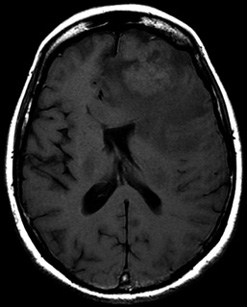

Entre circonvolutions et haustrations

Dr Karima Mokhtari GHP Salpêtrière - paris

Clinique :

Patiente âgée de 73 ans, ayant eu un adénocarcinome colique avec métastase hépatique, 6 ans avant l’histoire neurologique.

Syndrome frontal d’installation récente.

Quel est votre diagnostic ?